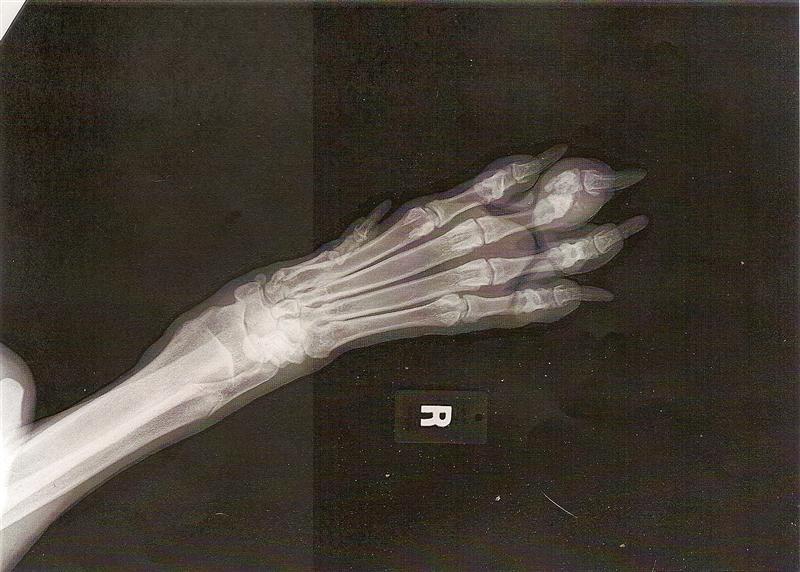

Last night I noticed swelling in one of Dana’s toes on her right front leg. She was not limping noticeably yet upon close examination; I noticed that it was painful to touch and Dana was SO good to allow me to look at her foot as closely as I did. I was worried about a puncture and then when I felt it and could see more; I started to be concerned about a break. I was out all day with Kinsley having had a Dentist appointment and then errands and Sean got home about 2 hours before I did and he did not notice anything ‘off’ with her. I suspected a possible broken toe and I booked an appointment for today and my poor doll face! 😥 I have scanned in one of the pictures of her foot below(I have copies for her complete medical records for when she does become adopted) and the middle phalange is a comminuted(crushing) fracture. You can clearly see all these bone fragments on the digital X-Ray(much harder in the scanned pic post below) and that it is just a mess. We spent quite some time ‘speculating’ the possible cause of this and the Vet said it looks like a Horse stepped on her yet that was not possible(she was inside all day) and had not been near the horses since the weekend plus if a horse had stepped on her; the Vet and I agreed that it would have been more than one toe crushed. We also discussed could she have caught it in a tree ‘root’ in the newly fenced in area; possible yet not likely. Sean and I walk that area daily to take note of the areas for probable ‘diggers’ etc. and we have not noted any hazards that could be the cause of this and I just wish she could speak!!! The other theory is that one of her bestest of friends; 200 pound Guinness stepped on it. She was such a happy camper at the Vet, with tail plus butt wagging that would rival BHRR’s Mazda! 😛 The Vet could not believe how she would literally walk pretty much normally on her foot too. WHAT a trooper! She is just so friendly and social to everyone and I know that she would have loved playing with the Vet’s dog(they have gotten along so famously since they originally met when I first brought in Dana last November) yet she was mildly sedated to X-Ray(she had to go up on the table and the angle of the foot) yet she lied in my arms very quietly and trustingly. MY best news is her weight!!!! When BHRR’s Dana first arrived on November 27th, 2008; she was a starved 29.2 KGS (64.24 pds). Her weight tonight was a very healthy, conditioned and gorgeous 51.40 KGS (113.08 pounds)!! The Vet said she looked amazing with her shiny black coat and that she is just perfect with her weight! YOU GO DANA!!!! This means that Dana has put on 48.84 pounds since her arrival to our program and home!!!! YAY! For Dana! In respect to her toe; we discussed splinting yet that was not really feasible and so, it is expected to heal just fine within 6 weeks or so and I will monitor closely. She is on Deramaxx 100 MG SID(I might split it to 50 MG BID for comfort for her) and rest…rest…rest. AND for anyone that knows Dana; that is like asking the sun not to rise or set. I had Sean pick her up on his way home around 6:30 PM for I was working until 8:00 PM and she has been resting comfortably in her crate since. I will not adopt her out at this time until her toe heals. So, she is on a HOLD right now…. Once she is back to 100%; I will make her available again. We are all so perplexed as to HOW this happened and man, what a happy girl she was FOR she has to just be in such pain. I; well know what it is like to have broken bones in my foot; compliments of BHRR’s Henry breaking my foot in 4 places; including a spiral fracture and it is not fun.

BHRR’s Dana – right front foot – June 10th, 2009 –Â middle phalange, comminuted(crushing) fracture